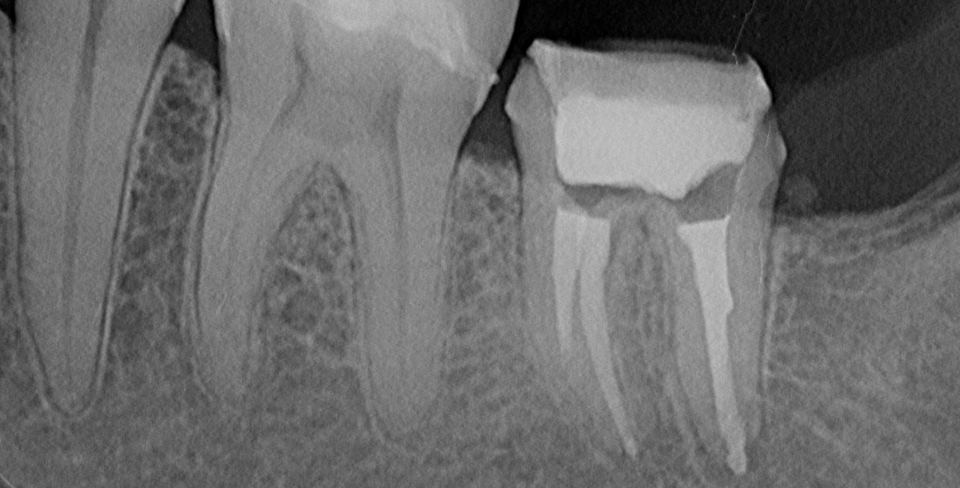

Es ist schwer zu glauben, aber „Wurzelkanäle verursachen Krebs?“ ist eine echte Frage, die sich viele Patienten stellen, nachdem eine Dokumentation über Netflix mit dem Titel Root Cause ausgestrahlt wurde und sich für eine endodontische Therapie ausgesprochen hat, die mit einem Anstieg der Krebsraten in Zusammenhang steht. In diesem kurzen Artikel wird versucht, die in diesem Dokumentarfilm erhobenen Vorwürfe auf drei Ebenen zu entlarven, damit ein intelligentes Gespräch mit Ihren aktuellen und potenziellen Zahnarztpatienten geführt werden kann.

Die Theorie der diskutierten Ursachen dokumentarischen die Fokalinfektion Theorie legt nahe , dass chronische Krankheiten , die durch lokalisierte Infektionen verursacht werden. In der Dokumentation wurde diese Theorie als Grundlage verwendet, um festzustellen, dass eine chronische Entzündungsreaktion induziert wird, da nicht alle Bakterien in einem mit Wurzelkanal behandelten Zahn entfernt werden können. Es wurden Behauptungen aufgestellt, dass die mit diesen mit Wurzelkanal behandelten Zähnen verbundene chronische Entzündung zu systemischen Erkrankungen wie Krebs, Arthritis, Herzerkrankungen, chronischer Müdigkeit und Impotenz bei Männern führte.

Da die Ursache für die Ätiologie der apikalen Parodontitis vor 100 Jahren nicht bekannt war, waren die Wurzelkanalbehandlungen sehr unterschiedlich, es wurden keine Protokolle erstellt, und die zu diesem Zeitpunkt durchgeführten Wurzelkanäle können nicht mit den heute durchgeführten Wurzelkanälen verglichen werden. Die modernen Konzepte der Endodontie, die Zahnärzte heutzutage anwenden – wie Spülen, Medikamente und mikroskopisches Debridement -, wären vor 100 Jahren keine gängige Praxis gewesen. Es wurde festgestellt, dass die Theorie der fokalen Infektion fehlerhaft war, da in den von Dr. Price durchgeführten Studien keine Kontrollgruppen vorhanden waren und Voreingenommenheit festgestellt wurde. Insgesamt hatte schlechtes experimentelles Design. Selbst wenn Sie immer noch an diese 100 Jahre alte Theorie glauben, würden die Wurzelkanaltechniken der Neuzeit nicht die gleichen Bakterien im Zahn zurücklassen wie die Wurzelkanäle, die vor einem Jahrhundert durchgeführt wurden.